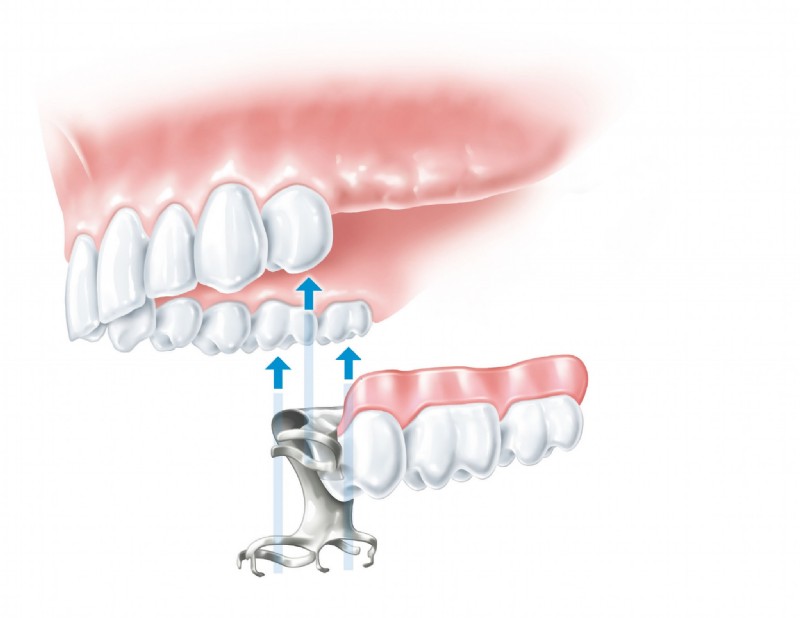

Als Spezialisten auf dem Gebiet der Implantologie wissen wir, wie man hochwertige Implantate stress- und schmerzfrei einsetzt und, wenn erforderlich, zuvor den Knochen aufbaut. Grundlegend werden in einem Beratungsgespräch all Ihre Fragen geklärt. Erst wenn Sie Vertrauen gefasst haben beginnen wir mit der professionellen Behandlung. Wir bieten Ihnen Einzelzahnimplantate, Brücken auf zwei oder mehreren Implantaten, zahnlose Kieferversorgung mit Implantaten, Brücken oder Halteelemente für Prothesen sowie maßgeschneiderte Lösungen für jedes individuelle Problem.

Hochqualitative künstliche Zahnwurzeln können natürliche Zähne sehr effektiv ersetzen. In einem ersten Schritt wird das Implantat-Bett aufbereitet, sodass das Implantat – eine Schraube aus Reintitan – problemlos in den Kiefer geschraubt werden kann. So können einzelne Zähne ersetzt oder Prothesen fixiert werden.